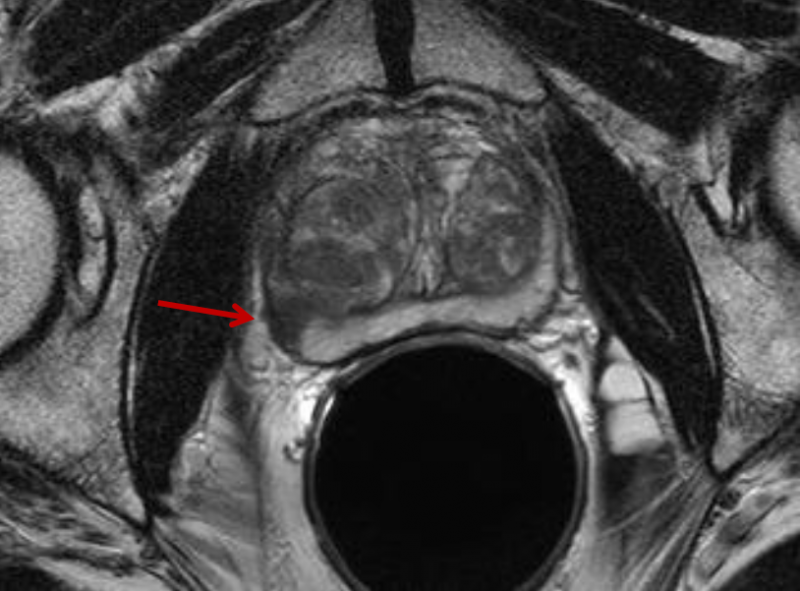

The Arthritis Foundation awarded $1 million to the Hospital for Special Surgery in New York City, University of California-San Francisco (UCSF) and Mayo Clinic in Rochester, Minn. to validate the use of new magnetic resonance imaging (MRI) techniques and newly identified biomarkers.

Fabry disease can be detected using a new magnetic resonance imaging (MRI) technique that was developed at the University of Alberta. The discovery of this new diagnostic tool has resulted in updated clinical guidelines for the diagnosis and treatment of Fabry disease in Canada.